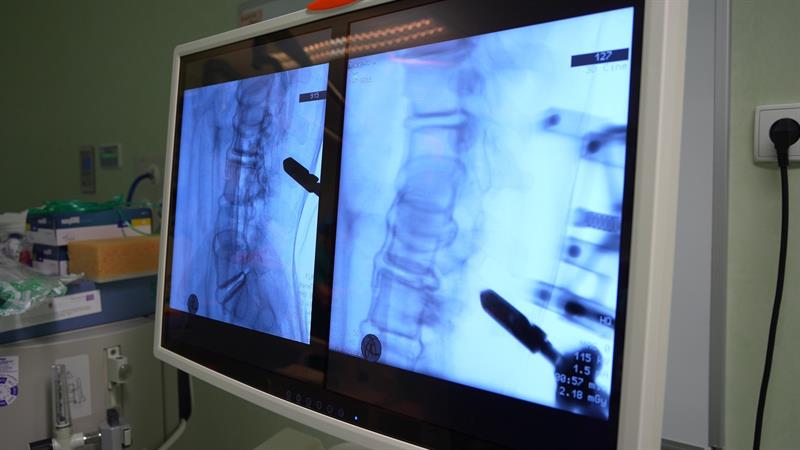

Fot. Szpital Wojewódzki w Szczecinie

Szpital Wojewódzki w Szczecinie w lutym ubiegłego roku był trzecim szpitalem w Polsce, w którym pacjenci wymagający operacji kręgosłupa byli operowani z użyciem systemu nowoczesnej robotycznej nawigacji. Od tamtej pory tutejsi neurochirurdzy wykorzystali go przy ponad 100 zabiegach. Ponadto, jako pierwsi w kraju, wykorzystali robota przy operacji szyjnego odcinka kręgosłupa u pacjenta, który doznał złamania w wyniku urazu. W tym przypadku doświadczenie zespołu operacyjnego wspierane precyzją ramienia robotycznego pozwoliły na bezpieczne ustabilizowanie złamanego kręgosłupa.